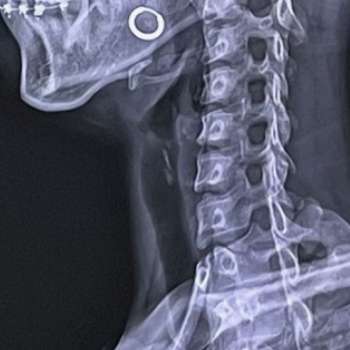

목디스크 증상 10가지

목디스크(경추 추간판 탈출증)는 목의 추간판이 탈출하거나 파열되어 주변 신경을 압박하는 질환입니다. 이로 인해 다양한 증상이 나타날 수 있으며, 각각의 증상은 환자에게 심각한 불편을 초래할 수 있습니다. 아래는 전문가적 입장에서 목디스크의 주요 증상 10가지를 상세히 설명하겠습니다.